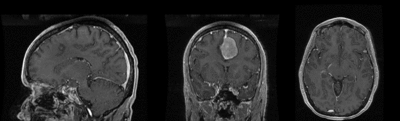

Slicer Registration Use Case Exampe #2: Inter-subject Brain MRI: axial T1 Tumor Growth Assessment

This is a classic case of change assessment. We want to know if the tumor changed since last exam.

MRI, brain, head, intra-subject, T1, tumor growth, meningioma, change assessment

reference/fixed : T1 SPGR , 0.9375 x 0.9375 x 1.4 mm voxel size, axial, RAS orientation.

moving: T1 SPGR , 0.9375 x 0.9375 x 1.2 mm voxel size, sagittal, RAS orientation.- Content preview: Have a quick look before downloading: Does your data look like this? Media:RegUC2_lightbox.png

- result screenshots (compare with your results)

- result evaluations (metrics)